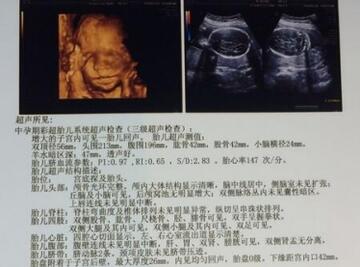

根据b超数据,宝宝双顶径数值比股骨长度数值>2,一般是男孩,因为说明宝宝脑袋比较大,这条对我是成立的。